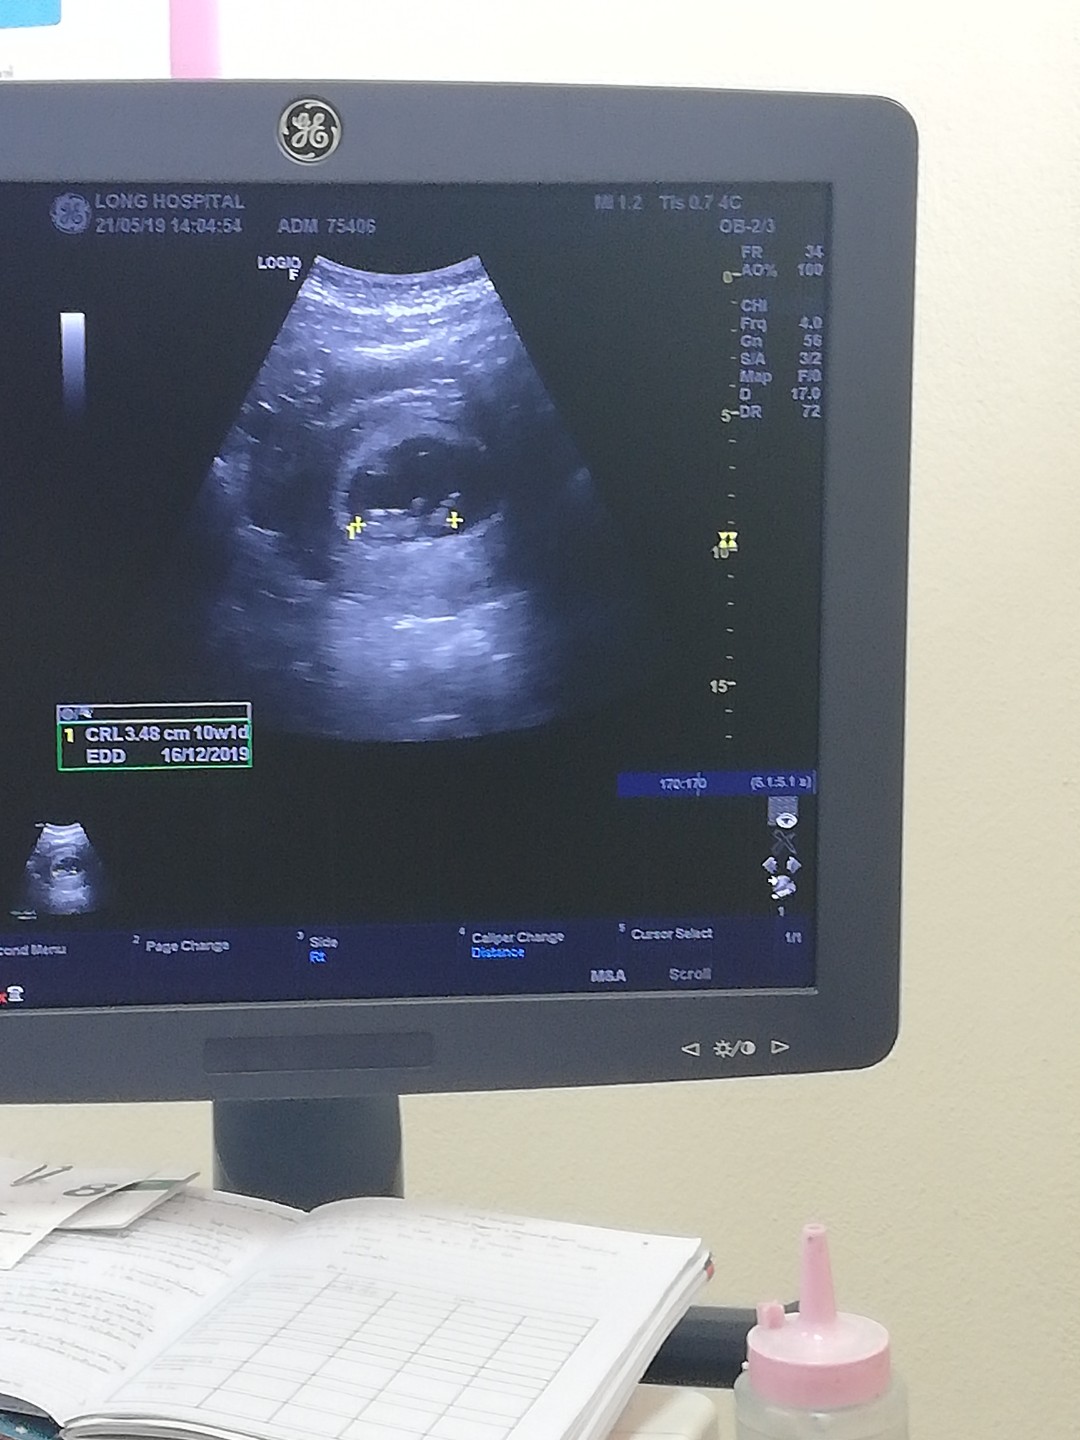

ตอน 10w ค่ะ